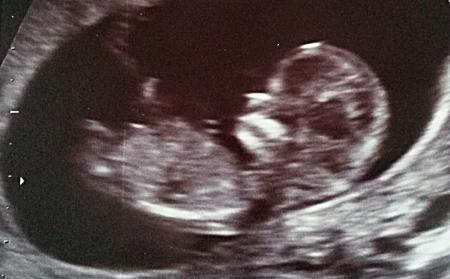

Bei mir wurde gestern bei 12+0 ein US gemacht, leider über den Bauch die Nackenfalte angesehen, weil das Kind doof lag. Weiß jemand, ob auf diesem Bild die Nackenfalte zu sehen ist?

Bild zu Sieht man hier die Nackenfalte? - Schwanger - wer noch? Rund um die Schwangerschaft

Klar kann man die da sehen, warum meinst Du, dass nicht?

Weil er leider über den Bauch schallen musste und ich mich selber mit den Ultraschallbildern schwer tue. Er meinte, dass sie unauffällig aussieht.

Ja, die sieht man immer in der Seitenansicht (eben hinten am Nacken). Rausmessen kann man das natürlich nur mit dem US-Gerät. Wenn er sagt, sie ist unauffällig, ist doch alles ok.